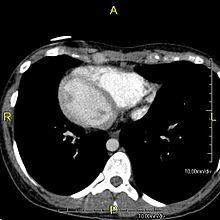

| Situs inversus causes the positions of the heart and lungs to be mirrored. | |

Situs inversus is found in about 0.01% of the population, or about 1 person in 10,000. In the most common situation, situs inversus totalis, it involves complete transposition (right to left reversal) of all of the viscera. The heart is not in its usual position in the left chest, but is on the right, a condition known as dextrocardia (literally, "right-hearted"). Because the relationship between the organs is not changed, most people with situs inversus have no medical symptoms or complications.[1]

Effect on anatomy

The condition affects all major structures within the thorax and abdomen. Generally, the organs are simply transposed through the sagittal plane. The heart is located on the right side of the thorax, the stomach and spleen on the right side of the abdomen and the liver and gall bladder on the left side. The heart's normal right atrium occurs on the left, and the left atrium is on the right. The lung anatomy is reversed and the left lung has three lobes while the right lung has two lobes. The intestines and other internal structures are also reversed from the normal, and the blood vessels, nerves, and lymphatics are also transposed.

If the heart is swapped to the right side of the thorax, it is known as "situs inversus with dextrocardia" or "situs inversus totalis". If the heart remains on the normal left side of the thorax, a much rarer condition (1 in 2,000,000 of the general population), it is known as "situs inversus with levocardia" or "situs inversus incompletus".

Diagnosis of situs inversus can be made using imaging techniques such as x-ray, ultrasound, CT scan, and magnetic resonance imaging (MRI).[6]